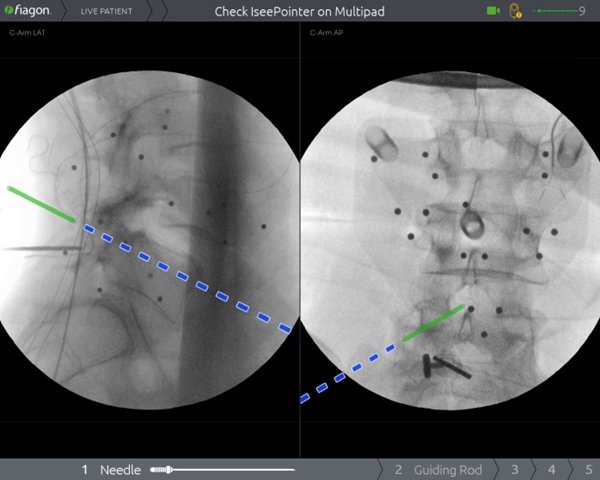

过去,受限于技术和设备,在脊柱上做手术,犹如在“暗箱”内操作,需要反复进行X线透视来判断术中状况,手术时间长,神经、血管损伤风险大。脊柱手术通常需要置入多枚螺钉,在没有先进设备辅助的情况下,医生只能凭经验操作,增加了相应的手术风险。脊柱手术的精准性和安全性一直是医生和患者最为关注的问题。而Joimax电磁导航系统作为目前世界最知名的导航系统,无传统光学导航系统“红外线遮挡”问题,并且不占用手术空间、可弯曲器械能实现尖端导航、定位器小巧,能实现多节段同步导航。骨二科(脊柱外科)李浩鹏主任表示,将导航系统应用于脊柱手术中,可以为医生呈现实时、直观的三维影像导航信息,帮助医生准确规划和及时更新手术方案,提高置钉的准确性,降低误伤神经、血管的风险,有效减少手术并发症,缩短住院时间,帮助患者及早恢复日常生活。

2020年1月9日,骨二科(脊柱外科)王栋教授团队成功将电磁导航技术引入到脊柱手术中,开展了医院首例电磁导航腰椎后方椎间融合术(PLIF)和首例电磁导航经皮穿刺椎体成形术(PVP)。手术当日,通过简单的安装信号发射器、定位仪并进行2D影像认证后,王栋教授团队在导航的辅助下,轻松完成原先脊柱手术中风险巨大的椎体植钉过程,随后的椎管减压及水泥注入等步骤一气呵成,有效缩短了手术时间、术中投射次数,大大降低了手术风险。